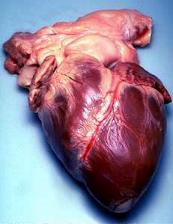

وزن القلب يبلغ 0.5% من وزن جسم الإنسان أي أنه بحدود 350 جرام لشخص يزن 70 كج ويمكن لهذا الوزن أن يزداد بزيادة عمله كما عند الرياضيين. يترافق هذه الزيادة الوزنية بازدياد حجم الدم الذي يضخ في النبضة الواحدة فما يزداد عند الرياضيين هو كمية الدم التي تضخ وليس عدد النبضات.

يحتوي القلب على أربعة حجيرات منفصلة تدعى: الأذينين اليمنى واليسرى والبطينين الأيمن والأيسر. تكون جدران الأذينين رقيقة نسبيا لأن طبيعة عملها الأساسي كمستودع للدم ومدخل للبطين فهي لا تقوم بعمل الضخ الأساسي الذي يتكقل به البطين. جدران البطين تكون أثخن لأنه يقوم بعملية الضخ الأساسية في الدوران الرئوي والدوران المحيطي.

يتكون القلب بصورة أساسية من عضلة تسمى عضلة القلب أو عضل القلب، التي تكوِّن جدار القلب والحاجز الذي يفصل بين الجانبين الأيمن والأيسر للقلب. وكل عضلات القلب تنقبض وتتمدد وتدفع الدم عبر القلب. يغطي القلب من الخارج غشاء يسمى النخَاب ويحيط غشاء آخر يسمى التّامور بالنخاب وبالقلب بصورة تامة وكاملة، ويمتد حتى أعلى القلب ليشمل الأوعية الدموية الممتدة أعلى القلب. وتوجد مادة لزجة بين التامور والنِخَاب تساعد القلب على الانقباض بسهولة. تختلف عضلة القلب عن عضلات الجسم الأخرى مثل العضلة الملساء والعضلة الهيكلية. فالعضلات الهيكيلية مثل التي في الذراع أو الرِجل لها ألياف طويلة وشرائح داكنة اللون وأخرى فاتحة بالتبادل، ويسمى هذا بالتخطُّط. ونحن نستطيع أن نتحكم في العضلة الهيكلية. أما العضلات الملساء التي تكون جدار المعدة الداخلي والأمعاء ومعظم الأعضاء الداخلية للجسم فخالية من التخطط وتعمل بحركة تلقائية ولا نستطيع أن نتحكم فيها. وعضلات القلب لها تخطُّط مثلها مثل العضلات الهيكلية. ولكنها تنقبض وتتمدد بحركة تلقائية مثل العضلات الملساء. وبالإضافة لذلك فإن خلايا عضلات القلب تعمل مجتمعة وكأنها خلية واحدة. فعندما تنقبض أو تتمدد أي خلية في القلب فإن الخلايا المحيطة بها تعمل الشيء نفسه، ولهذا السبب يخفق القلب أو يدق دائمًا وبانتظام مدة حياة الإنسان.